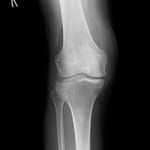

○ 脛骨高原骨折(プラトー骨折)

足を強く地面についた際に体の重みと下から突き上げる力により膝の関節周囲に骨折を起こします。

ちょうど土手が崩れるように折れています。通常は手術によりボルト打ち込み固定しますが、運よく関節面が維持されているので保存的(手術をしない)に治療することができました。

当初は関節内の骨折のため腫れがつよく安静処置が必要です。膝を包むような副子を作り包帯で固定。毎日当院の送迎により来院してもらい、湿布の交換、骨折部位の超音波治療、医療マッサージを施し現在も治療中。